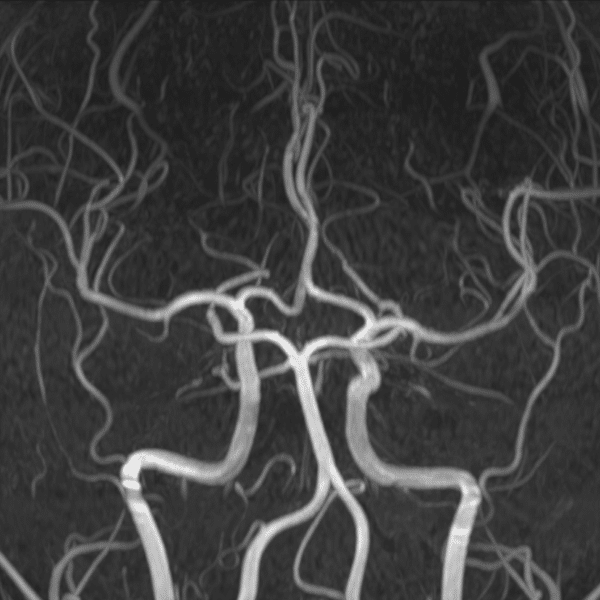

Brain MRA

3.0T Siemens MAGNETOM Skyra

3D TOF

(L) 0.5×0.6×1.2 mm,

(R) 0.5×1.0x1.2 mm, MIP

Conventional SwiftMR™ 07:12 03:13 (68% Faster)